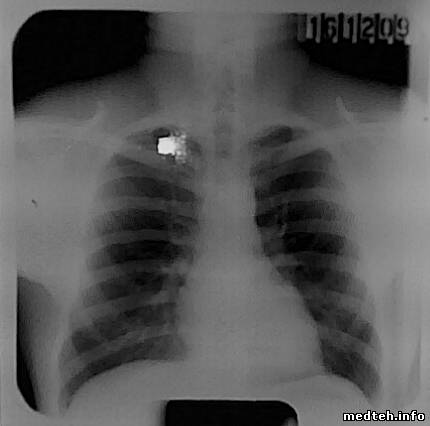

Вот 2 снимка сделанных сегодня.

Снятые люди худенькие, режим съёмки 90 КV 60 МАС и ток трубки при съёмке 102 и 100.

Что можно сказать о снимках?

Белые квадраты, это отблеск светодиода камеры сотового телефона при съёмке снимка.

снимок по степени почернения считаеться норма - если видно 3-4 верхних позвонка, качество должен оценивать рентгенолог

Показал сегодня снимки знакомому рентгенологу, который специализируется именно на флюорограммах, в другой организации.

Снимки были признаны годными, с небольшими замечаниями.

Некоторая небольшая нерезкость, и отсутствия номера карточки снимаемого.

Номер на карточке просто не писали, но проверить надо конечно,

а нерезкость, возможно, от шевелёнки снимаемого или я его неправильно поставил.

Снимали сами, рентгенлаборант уволилась, возможны варианты...